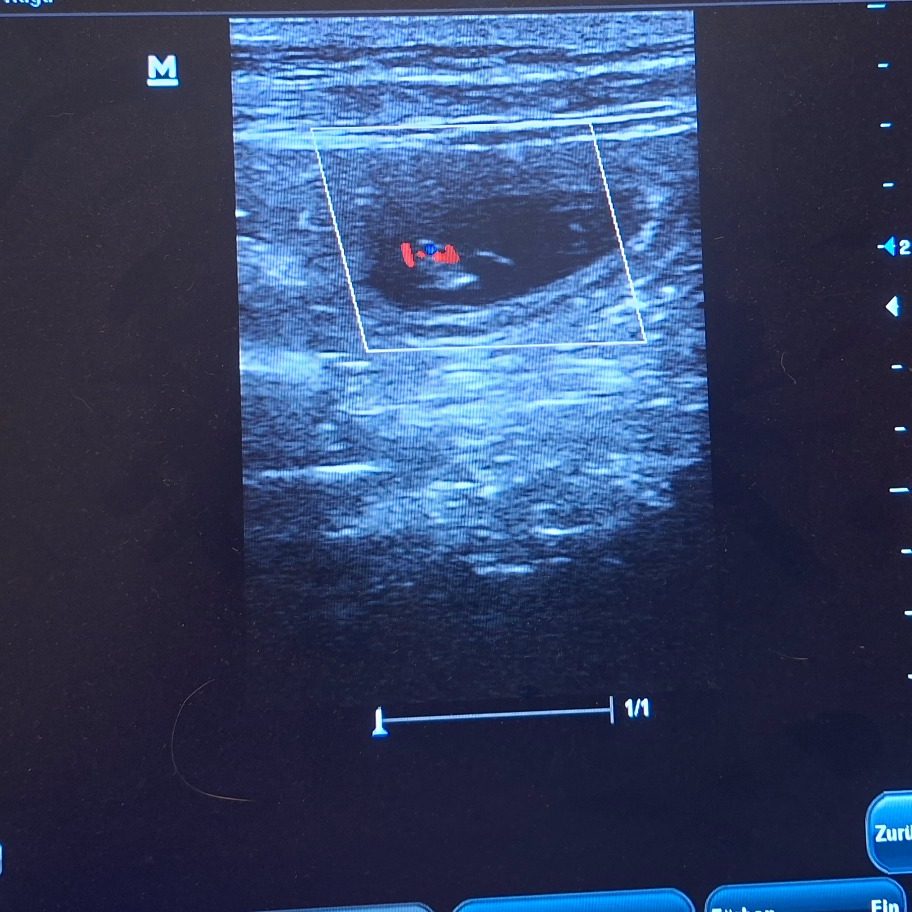

Endlich hatten wir den ersten Ultraschall und wir haben tolle Neuigkeiten

!!Kuba ist trächtig!!

Die letzten Tage waren für mich sehr sehr hart. Die Spannung war kaum auszuhalten. Ich wollte es jetzt endlich bestätigt haben, dass unsere Kuba trächtig ist. Ihr Verhalten und ihr Körper haben sich aber schon sehr verdächtig verändert. Sodass es heute eigentlich klar war, dass wir mit dem Ultraschall fündig werden. Wir haben nur einen kleinen Bereich geschallt und auch nicht lange, damit es für sie nicht zu anstrengend wird. Uns war nur wichtig zu sehen, dass es geklappt hat und die Kleinen leben. Alle Herzchen die wir gefunden haben schlugen ganz stark und alles sieht sehr gut aus.